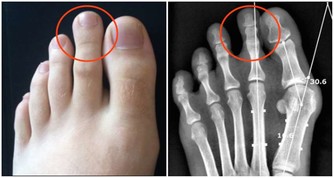

首先,我想從我個人過去各種關節病痛經歷中,最常聽到醫生說的──「退化性」關節炎談起。

★避免人工關節手術,鬆緩肌肉消除膝蓋痛

58歲魏女士,數年來以玻尿酸治療膝蓋傷,最後惡化到須換人工關節。

經調整並配合強化操後,不能彎的膝蓋終於可以蹲下。